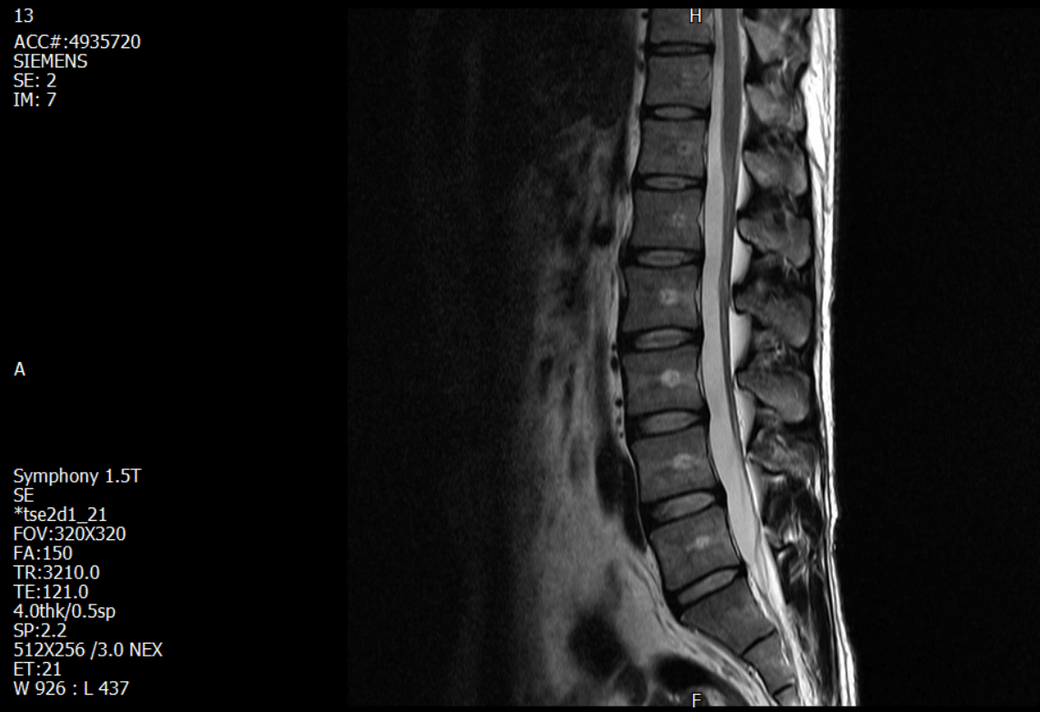

경추 요추 디스크 MRI판독 부탁드립니다.

-11월, 증상발생 직후 잠실소재 척추전문병원 MRI 요추경추 촬영 후 신경외과 박사 진료, 허리는 매우 건강, 경추는 퇴행성 진행되고 있지만 디스크라고 보기 어려움. 신경막만 살짝 건드리는 정도고 이 정도로 힘빠짐이나 저림이 오지 않고 원인은 다른 곳에 있을 가능성.

1. MRI 상 , 경추와 요추에 디스크가 있나요? 있다면 좌측 팔과 다리에 저림 및 힘빠짐을 줄 정도인가요?

2. 혹시 영상의 퀄리티가 떨어져서 의사끼리 의견이 다른것일까요? MRI는 1.5T로 촬영된 것인데, 3.0T로 재촬영할 필요가 있을까요?

• 1. MRI 사진을 보았을 때 디스크를 의심해볼 수 있는 소견이 살짝살짝 보이긴 합니다만, 상하지의 저림 및 힘빠짐을 유발할 정도인지는 솔직히 회의적입니다.

2. 영상의 퀄리티는 나쁘지 않아 보입니다. 굳이 재촬영을 하실 필요는 없어 보입니다.

4. 말씀하신 것처럼 특히 요추부 MRI는 디스크를 찾기 어렵습니다.

상기 MRI 소견으로는 심한 증상을 보일 정도는 아니며 디스크의 가능성은 적어보입니다.